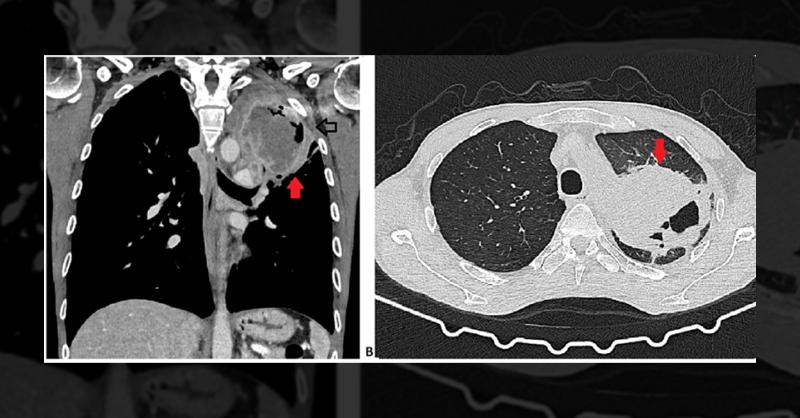

A 44-year-old male, a former smoker with a 21-pack-year history, presented arthralgia in his upper and lower limbs. Clinical examination showed pain, arthritis, and synovitis in knees, hands, and ankles. Blood tests indicated slight anemia (hemoglobin 11.2g/dL), leukocytosis (19.2/L), elevated CRP (4.20 mg/dL), and ESR (60 mm/hr). Immunology reveal

Challenging Diagnosis of a Patient with Digital Clubbing and Arthralgia